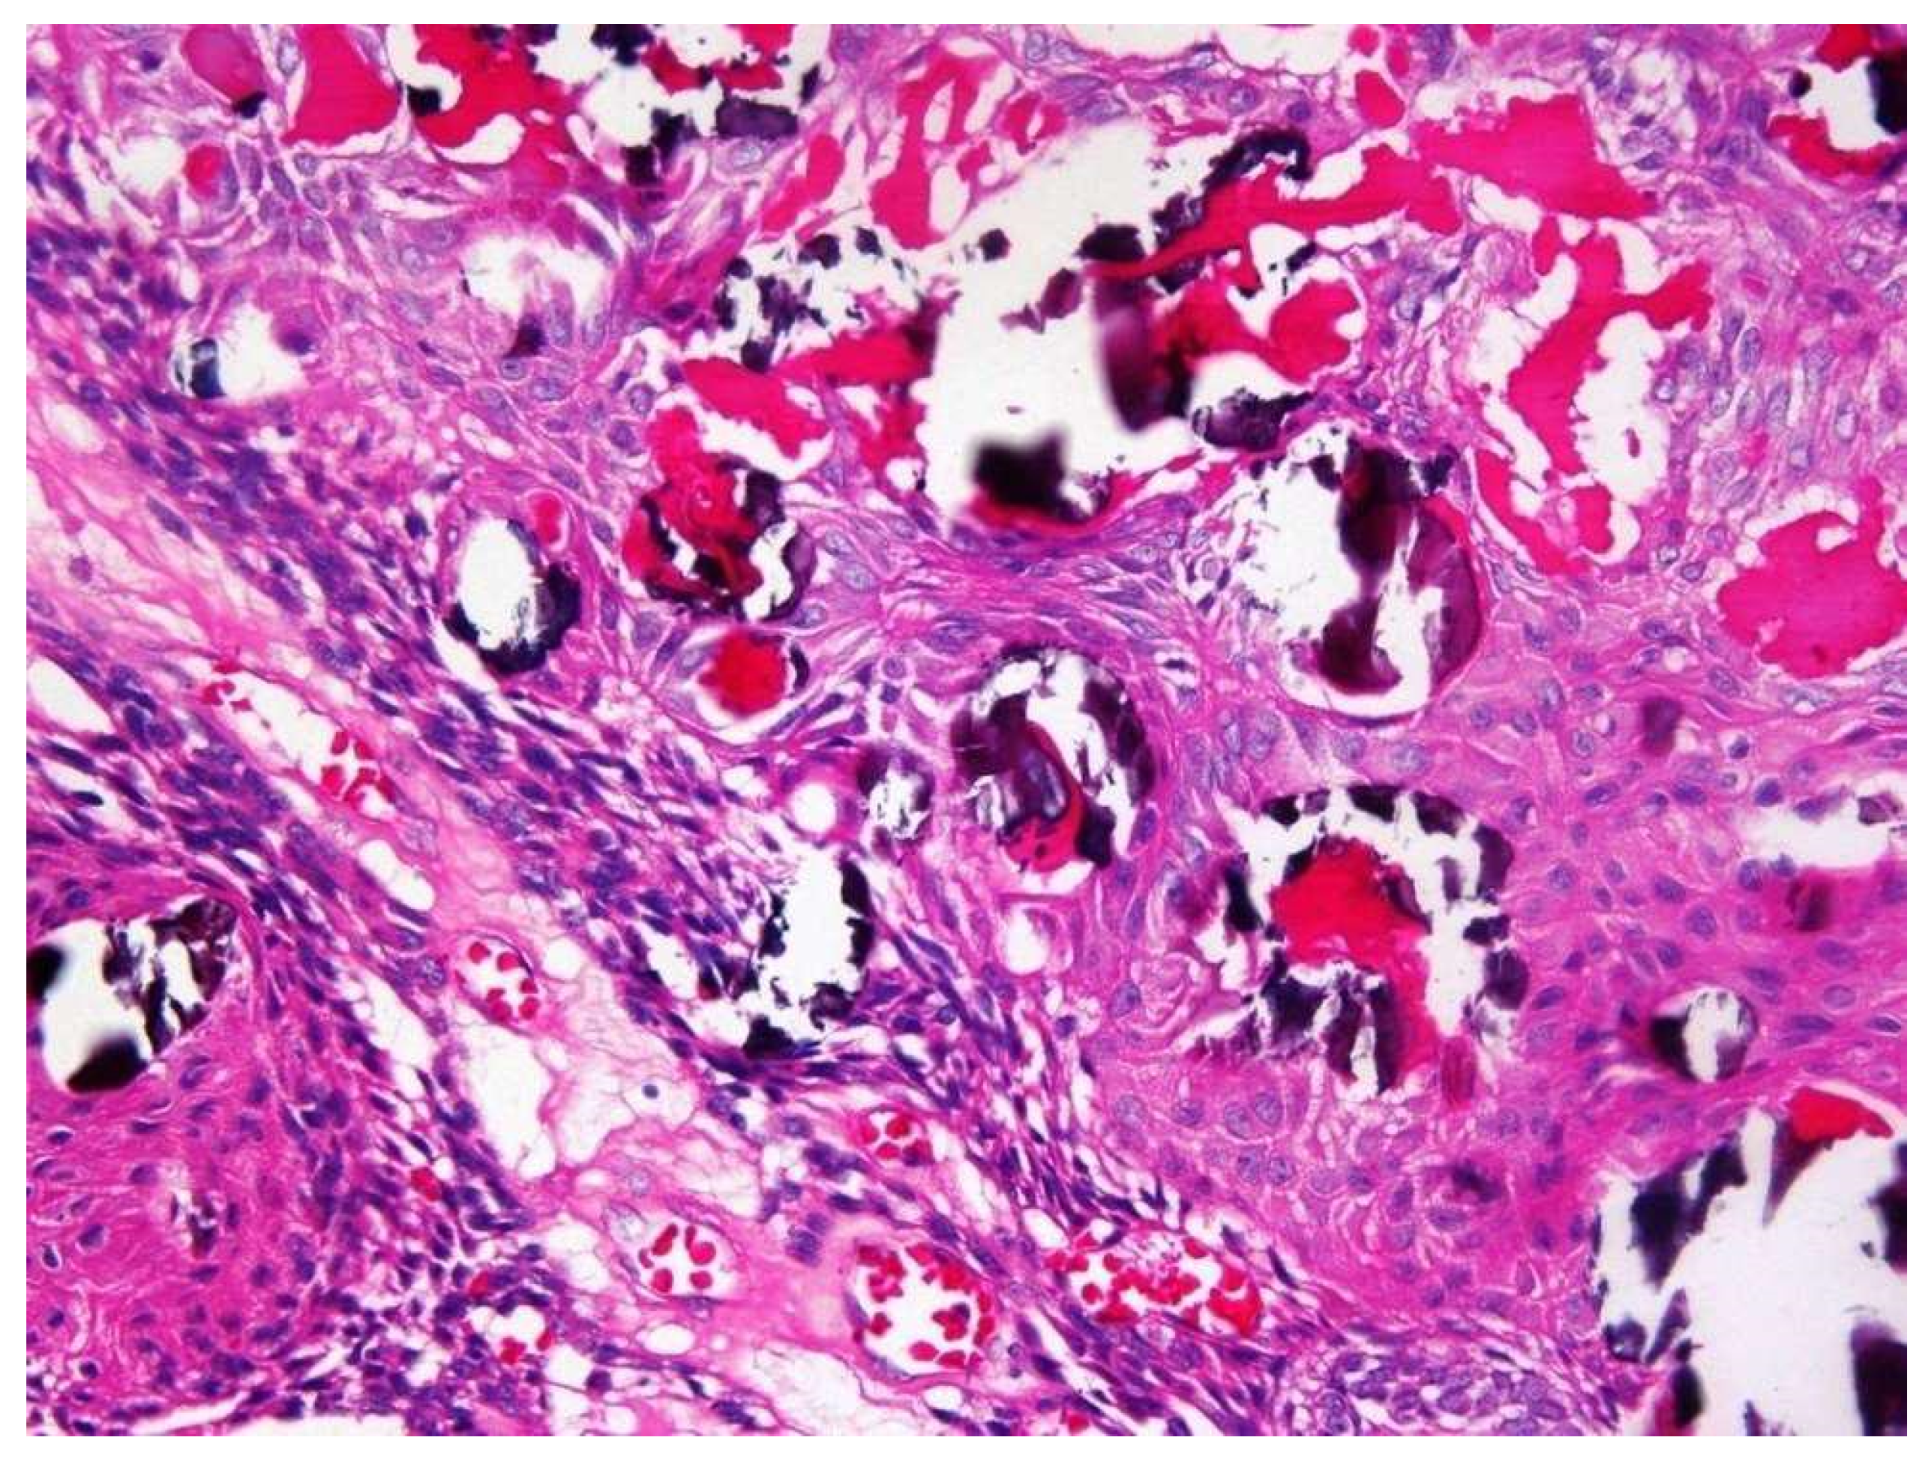

| Histopathology | ||||

| 1. Capsule-present | 10 (90.9) | 24 (80.0) | 34 | |

| 2. Epithelial component | ||||

| 2a. Duct like structures | 09 (81.8) | 27 (90.0) | 36 | |

| 2b. Epithelial whorls | 11 (100) | 29 (96.6) | 40 | p = 0.7 |

| 2c. Rosettes | 03 (27.2) | 19 (63.3) | 22 | |

| 2d. Trabeculae | 08 (72.8) | 25 (83.3) | 33 | |

| 3. Stromal component | ||||

| 3a. Tumour droplets | 08 (72.8) | 20 (66.6) | 28 | |

| 3b. Calcifications | 11 (100) | 29 (96.6) | 40 | p = 0.8 |

| 3c. Osteo-dentine | 01 (09.1) | 01 (03.3) | 02 | |

| 3d. Melanin | 00 | 01 (03.3) | 01 | |